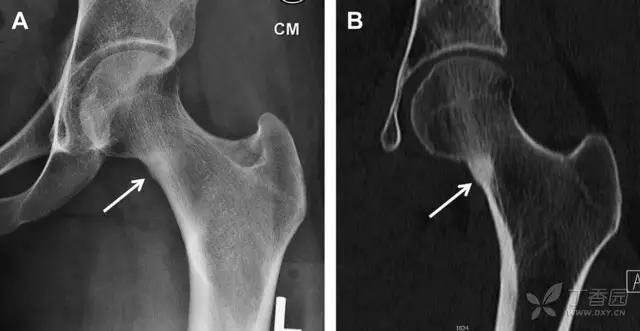

髋臼骨折最常见的类型是髋臼后壁骨折,几乎占髋关节骨折的 1/4,且常常合并髋关节后脱位。由于骨性结构重叠,可能肉眼看上去觉得非常轻微的骨折,事实却并非如此。髋臼后缘中断常常是髋臼后壁骨折的一个特征(图 2)。

图 2 为髋臼后壁骨折伴髋关节脱位患者。A 右侧髋关节 X 线片示股骨头后方可见一骨折线(箭头),髋臼后缘中断。B 左侧髋关节 X 片对照可见髋臼后缘连续(箭头)。C CT 三维重建图像示髋臼后壁缺损,可见旋转、移位的骨折块(箭头)